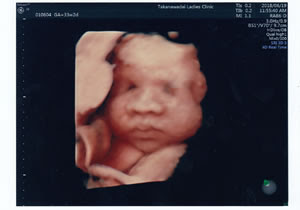

4d超音波検査 慶愛病院 産婦人科 北海道帯広市

3d 4dエコー 高輪台レディースクリニック 港区の産科 婦人科